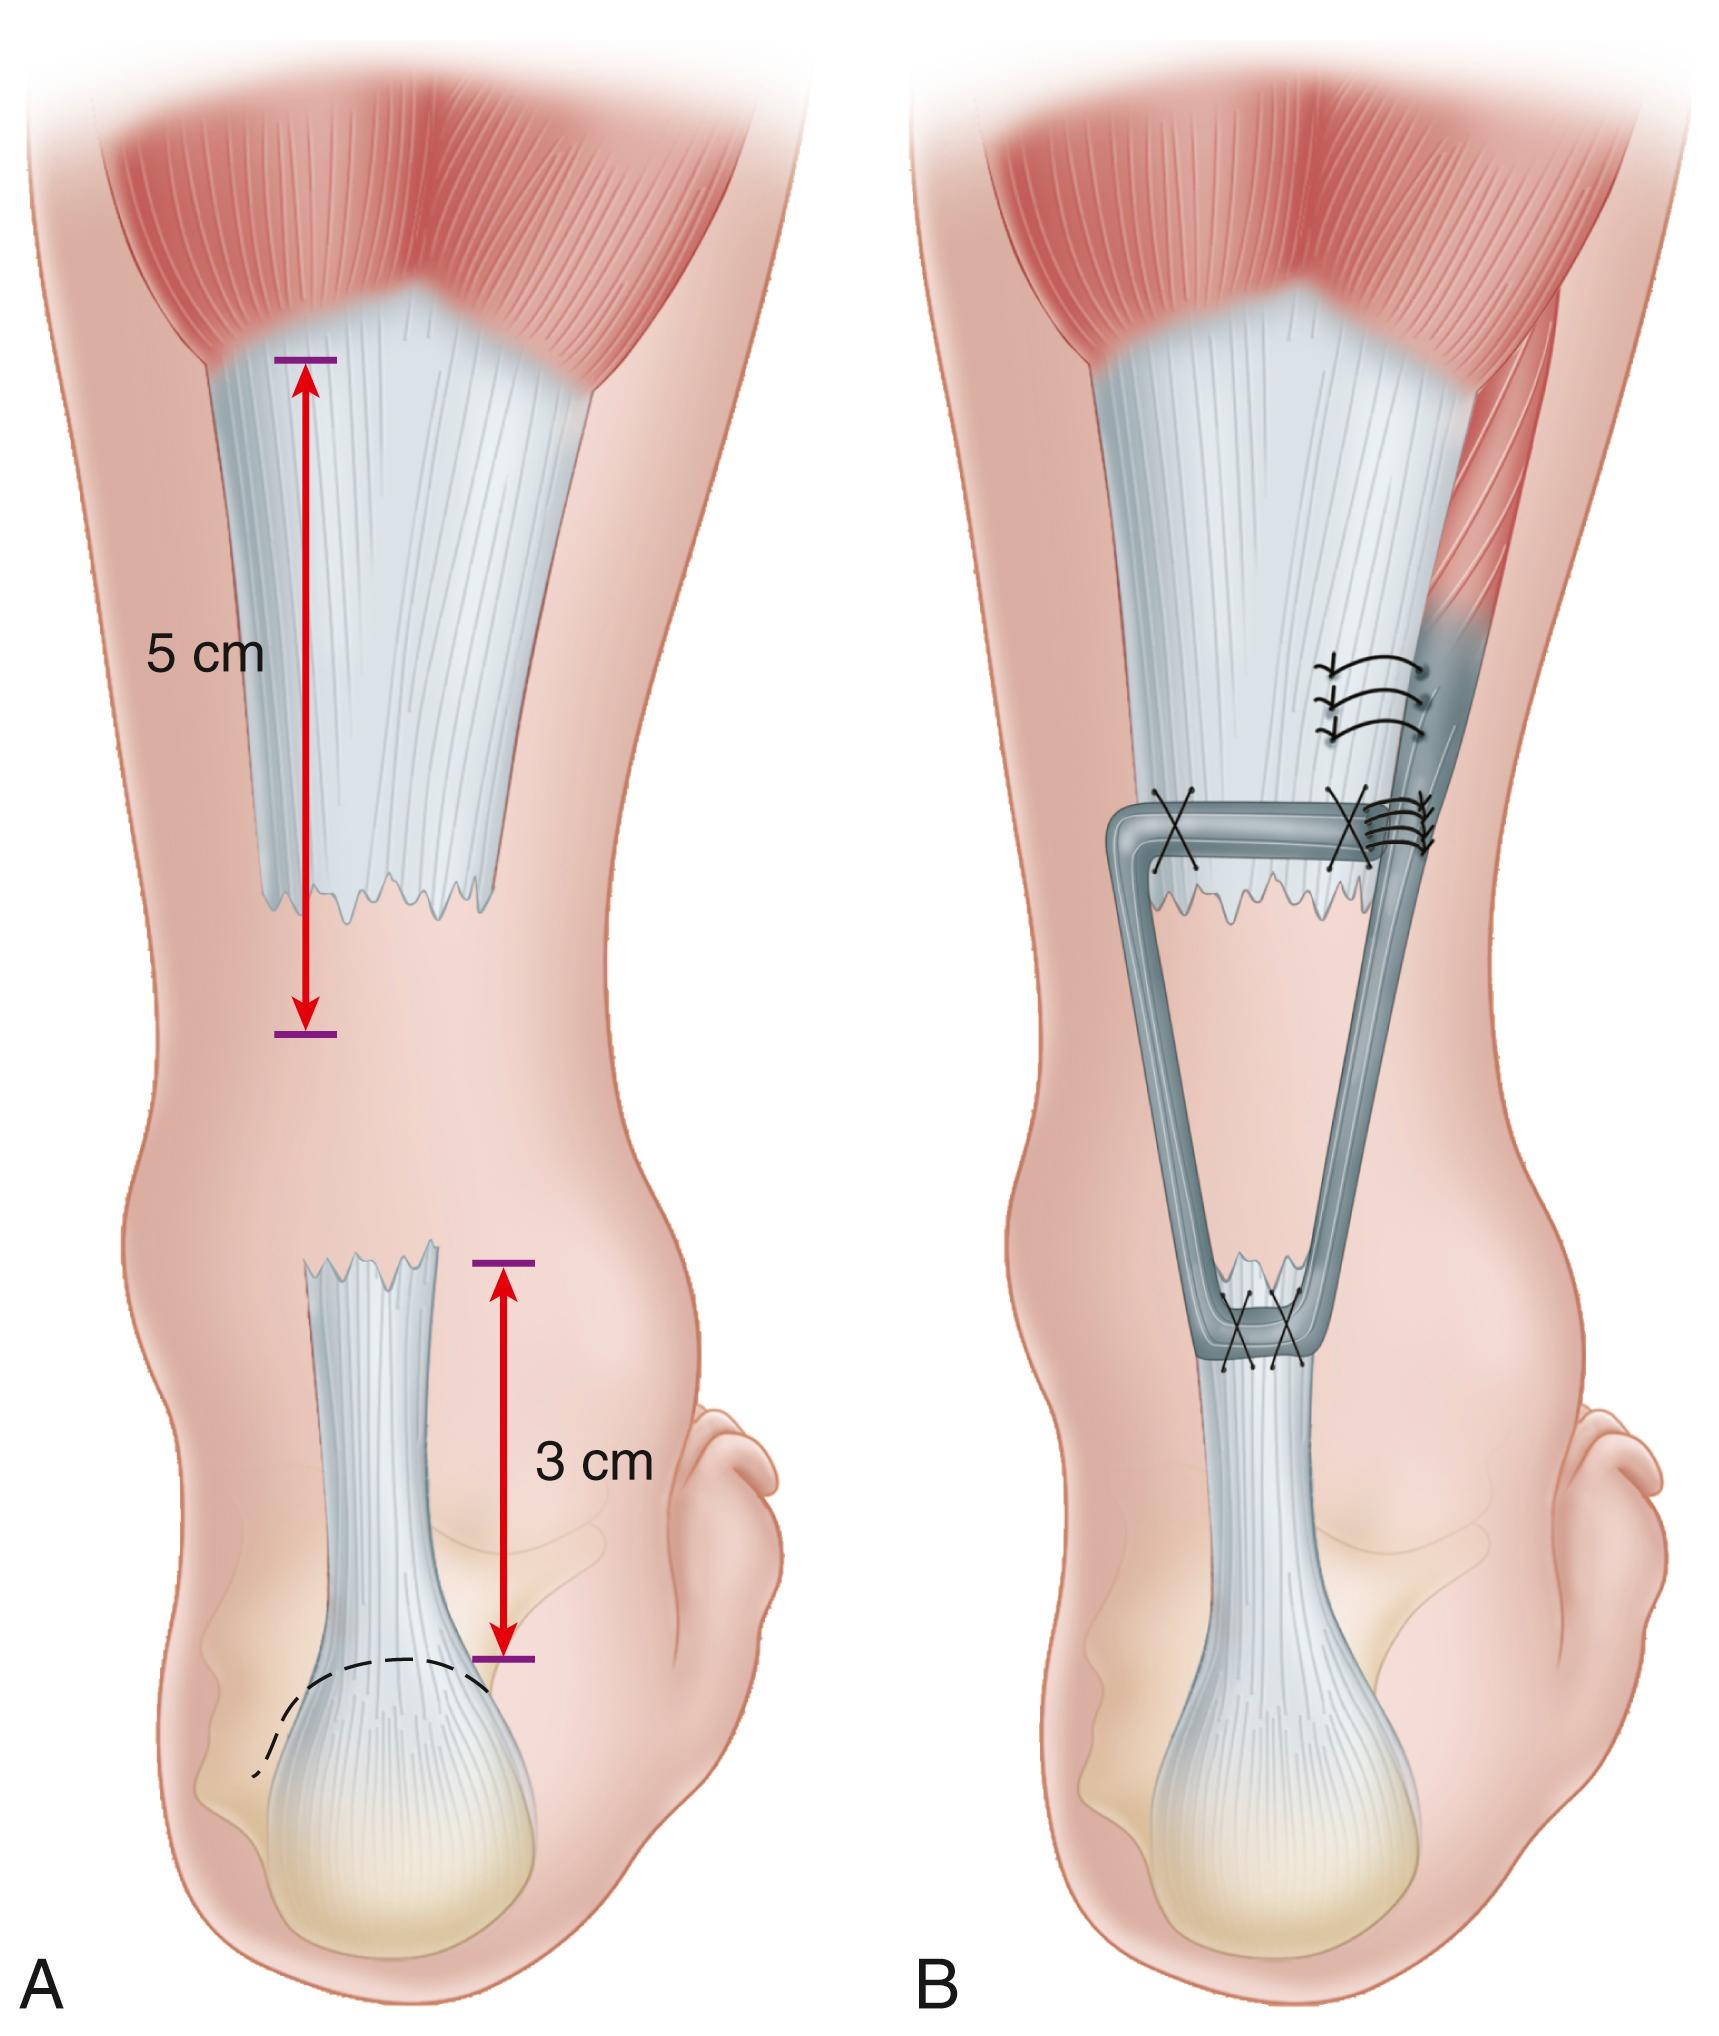

• Plantaris

• Posterior tibial

• Synthetic or allograft augmentation

• Polyglycol threads

• Marlex mesh

• Dacron vascular graft

• Carbon fiber

• Allograft tendon